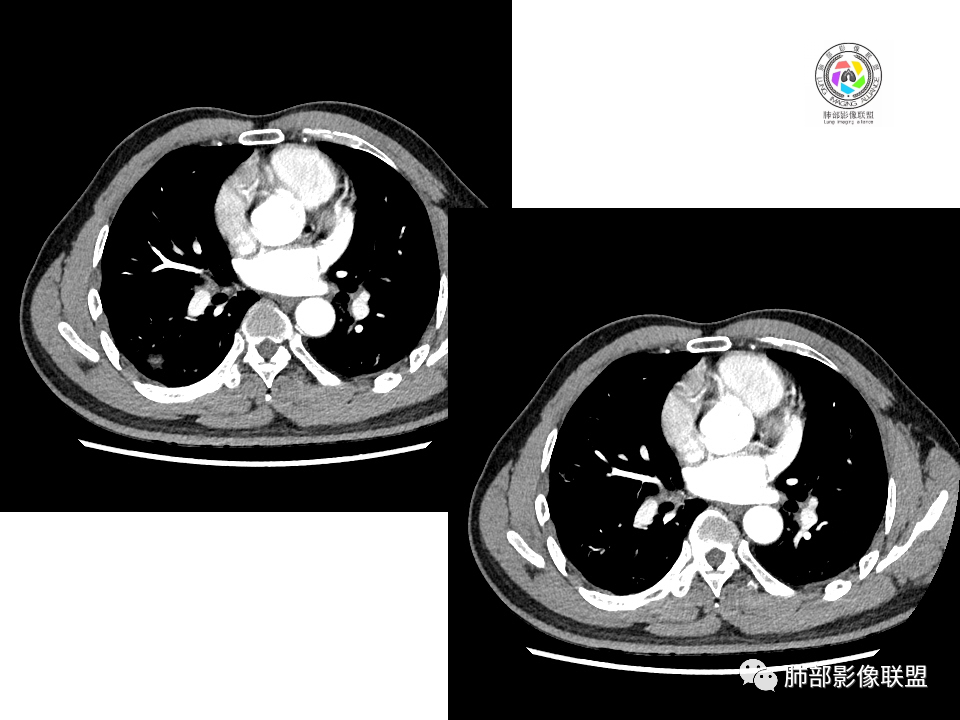

2.右肺下叶背段胸膜下块影,边界清楚光整,上下极见磨玻璃晕,未见明显分叶毛刺和棘状突起,未见胸膜凹陷或胸壁侵入。密度均匀,轻度不均匀强化。未见支气管进入。

4.右肺下叶基底段支气管血管束旁小结节影,边界清楚,强化不明显。注意,这结节在“遥远的”基底段。

血管也是稍推移,在边缘,病灶密度均匀,边缘稍收缩;均匀强化;

这两个病灶的密度、强化、形态、边缘、与血管的关系类似;还是一元论吧。

南边:这两个一元论的病灶考虑:

①炎性:隐球菌;

②恶性:间叶来源肿瘤,间叶来源的两个病灶的罕见;癌一般还是与支气管关系密切,有如果考虑癌,自然是小细胞癌(山丘征);但是因为没有看到支气管具体情况,不太踏实。